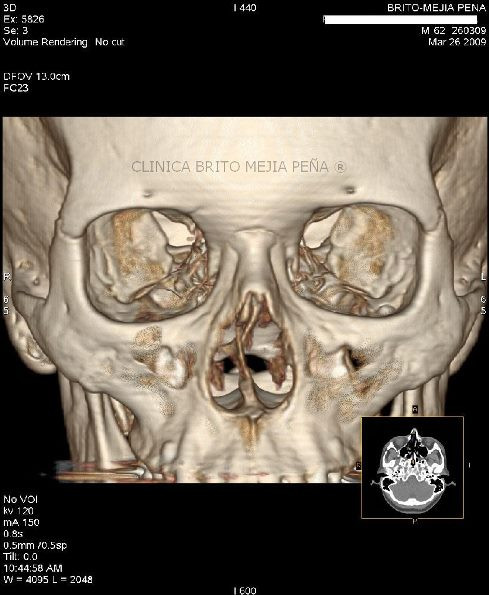

Fx piso órbita y hernia musculo

Fx piso órbita y hernia músculo sagital